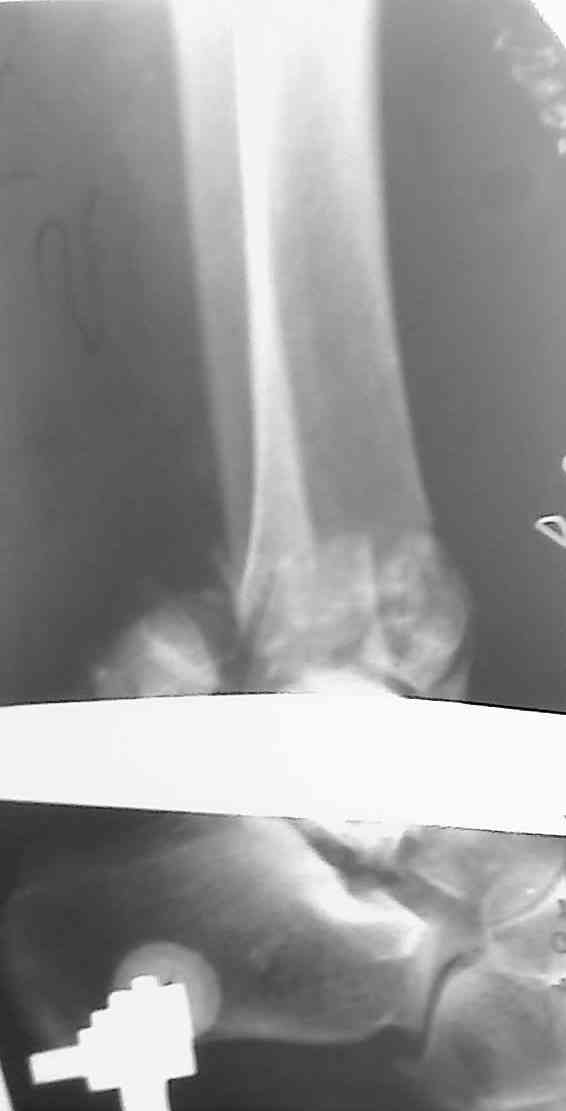

[Ortho] Перелом пилона

Уважаемые коллеги,прошу совета.

Девушка, 29 лет, падение с высоты 10 дней назад. Рентгенограммы в

приложении, КТ пока не готово, выложу по возможности.

Предполагается ORIF м/берцовой кости 1/3 трубчатой пластиной,

дистального конца б/берцовой - винтами + пластиной LCP.

Мнения коллег разошлись по следующим вопросам:1. Какие доступы выбрать,

с какого отдела начинать.

2. Облегчит ли работу дистрактор.

3. Потребуется ли костная пластика.